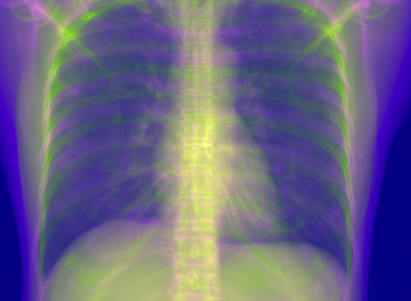

5.1 Chest Data

Refer to caption

(a) Reference

(b) 0superscript00^{\circ} perspective

(c) (b)-(a)

0.4237, -, -

0.4002, 17.01, 0.6532

Pix2pixGAN

(d) 0superscript00^{\circ} Cartesian

(e) 0&180superscript0superscript1800^{\circ}\&180^{\circ} Cartesian

(f) 0&180superscript0superscript1800^{\circ}\&180^{\circ} polar

0.4303, 7.08, 0.8535

0.4214, 5.37, 0.9098

0.4240, 3.83, 0.9536

(g) (d)-(a)

(h) (e)-(a)

(i) (f)-(a)

TransU-Net

(j) 0superscript00^{\circ} Cartesian

(k) 0&180superscript0superscript1800^{\circ}\&180^{\circ} Cartesian

(l) 0&180superscript0superscript1800^{\circ}\&180^{\circ} polar

0.4272, 10.92, 0.8222

0.4281, 9.37, 0.8424

0.4248, 8.12, 0.8859

(m) (j)-(a)

(n) (k)-(a)

(o) (l)-(a)

Figure 10: Perspective deformation learning in one exemplary patient case for chest X-ray imaging. The maximal horizontal cardiac diameter and the maximal horizontal thoracic diameter in (b) and (d)-(f) are indicated by the horizontal red lines, while those in the reference image (a) are green lines. The cardiothoracic ratio, RMSE, and SSIM for each image is displayed in its corresponding subcaption.

The results of one patient in chest X-ray imaging are displayed in Fig. 10, where the cardiothoracic ratio is assessed as an exemplary clinical application [32]. In the reference image (Fig. 10(a)), the maximal horizontal cardiac diameter (MHCD) and the maximal horizontal thoracic diameter (MHTD) are indicated by two green horizontal lines. Its cardiothoracic ratio is 0.4237. In the 0superscript00^{\circ} perspective projection image (Fig. 10(b)), all the anatomical structures can be visualized with fine resolution. However, due to perspective deformation, anatomical structures, e.g. the ribs and the spine, are deformed. The deformations are visualized better in the difference image Fig. 10(c). Compared with the ribs and the spine, the heart has less deformation as its location is closer to the isocenter. In Fig. 10(b), the MHCD and the MHTD are indicated by two red horizontal lines, while the green lines are those of the reference image. While the MHCD has changed little from 10.47 cm to 10.16 cm, the MHTD has changed considerably from 24.71 cm to 25.40 cm. As a consequence, the cardiothoracic ratio becomes 0.4002, which is below the normal range of 0.42 - 0.50 [32]. The result of learning perspective deformation from 0superscript00^{\circ} single view is displayed in Fig. 10(d), where the MHCD and the MHTD are 10.63 cm and 24.71 cm, respectively. The MHTD of Fig. 10(d) is the same as that of the reference image. This is also reflected by the difference image Fig. 10(g), where the lower ribs have small errors. However, the upper ribs as well as the spine still have considerable errors. The results of perspective deformation learning from 0&180superscript0superscript1800^{\circ}\&180^{\circ} views in Cartesian and polar coordinates are displayed in Fig. 10(e) and Fig. 10(f), respectively. The measured MHCDs and MHTDs in these two images are very close to the reference ones. Hence, their cardiothoracic ratios, 0.4214 and 0.4240 respectively, are close to the reference ratio as well. In the difference images (Fig. 10(h) and Fig. 10(i)), the errors of ribs and spine decrease as their boundaries are no longer apparently visible. Nevertheless, Fig. 10(i) has less error than Fig. 10(h), achieving the smallest RMSE value of 3.83. The quantitative evaluation of all the 162 testing datasets is displayed in Tab. II, where learning perspective deformation from two complementary views in polar coordinates achieves the least RMSE 4.98 and highest SSIM 0.9517, demonstrating the superiority of learning perspective deformation from two complementary views in polar coordinates.

The TransU-Net results are displayed in Figs. 10(j)-(l). Compared with their corresponding Pix2pixGAN results, the TransU-Net prediction images are more blurry, although the same perceptual loss is used. The error images in Figs. 10(m)-(o) indicate that TransU-Net reduces perspective deformation better with complementary views than a single view. The quantitative evaluation in Tab. II shows that TransU-Net cannot effectively reduce perspective deformation with a single view. With complementary views in both Cartesian and polar coordinate systems, TransU-Net achieves comparable performance, which is still considerably worse than that of Pix2pixGAN. The inferior performance of TransU-Net to Pix2pixGAN on the chest data is potentially caused by the repetitive nature of the segmental rib anatomy, which leads TransU-Net to be ineffective in extracting position-dependent features.